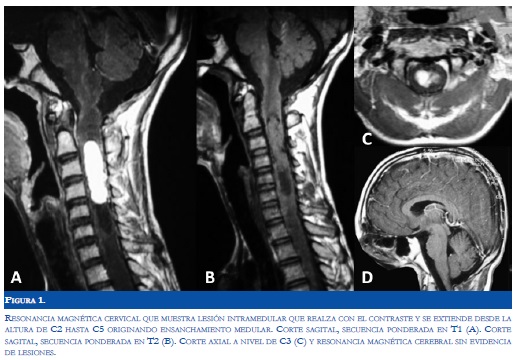

Paciente de sexo masculino de 16 años de edad, sin antecedentes patológicos relevantes, quién desarrolló dolor cervical asociado a espasmos musculares en dicha región, manejado hasta ese momento con medidas locales y analgésicos comunes. Dos meses después del inicio de estos síntomas, el paciente desarrolló monoparesia del miembro superior izquierdo y alteración sensitiva distal distal en el mismo miembro. Al ingreso a nuestra institución se encontró al paciente sin déficit en la esfera mental, ni alteraciones al examen físico general, pero con monoparesia de miembro superior izquierdo 2/5 y con hipoestesia ipsilateral en el dorso de la mano. Se realizó resonancia magnética (RM) de columna cervical en la cual se evidenció una lesión medular intraaxial cervical que comprometía desde la altura del cuerpo vertebral C2 hasta C5, de intensidad mixta y que captaba activamente el medio de contraste, sin evidencia de nido vascular (Figura 1). Con base en lo anterior, se consideró la posibilidad de una neoplasia intramedular altamente vascularizada. La arteriografía medular cervical permitió observar una lesión neoplásica con vascularización tipo capilar y con drenaje por venas dorsales prominentes y permitió descartar la posibilidad de una malformación arteriovenosa (Figura 2).